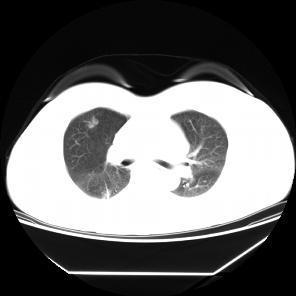

患者,女,57岁,因“右肺占位”于2015-09-17 15:08入院。 患者缘2月前体检无意发现右肺占位,伴随症状:无咳嗽、咳痰、无胸闷、胸痛、气短,无头晕、视物旋转,无恶心、呕吐,无腹痛、腹泻,无尿急、尿频、尿痛,2015-7-1 CT示:1.右肺上叶前段及下叶背段结节伴实变,右肺下叶结节见支气管气相征,考虑炎性病变可能,建议治疗后复查除外肿瘤性病变;双肺多发炎症;2.双侧胸膜肥厚;肺动脉增宽,提示肺动脉高压;3.肝左外叶小囊肿;4.甲状腺双叶增大,考虑为甲状腺肿,请结合临床。2015-9-2复查CT示:1.右肺上叶前段结节较前片无明显变化;右肺下叶背段结节较前片增大,建议进一步检查除外肿瘤性病变;双肺多发炎症较前片吸收;2.双侧胸膜肥厚;肺动脉增宽;3.肝左外叶小囊肿;4.甲状腺肿大,同前片。以“右肺占位”收住院,自发病以来,食欲减低,体重无明显下降,大小便无异常。

患者无任何症状,体检发现肺部小结节影,观察2月,未见缩小,似有轻度增大,入院后经CT引导下肺穿刺活检提示高分化腺癌,行手术治疗。 周围型肺癌早期影像学表现为孤立的肺内结节或肿块,通常有分叶征,毛刺征,空泡征,支气管充气征,坏死液化或空洞形成。此患者仅表现为淡薄的渗出影,小结节影,观察2月没有变化后,经穿刺证实肺癌,因此对肺部小结节影,斑片影,不吸收,无钙化的要特别注意肿瘤可能。